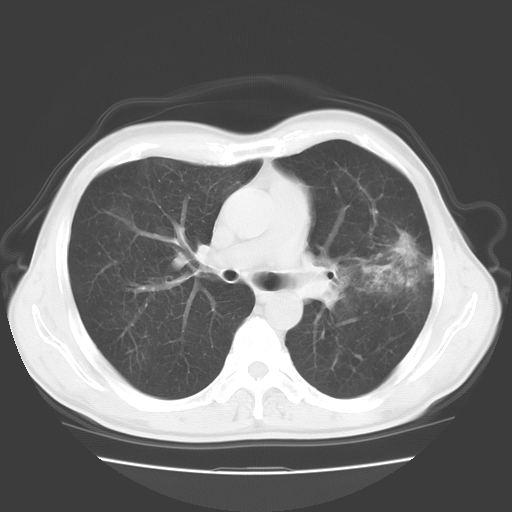

以下是引用随光逐影在2008-11-20 23:02:00的发言:[br]1)考虑左肺上叶周围型肺癌可能性大。2)两肺散在性肺泡积血。[br][br][本贴已被 随光逐影 于 2008-11-20 23:09:31 修改过]

以下是引用drzhang8888在2008-11-20 22:20:00的发言:[br]密集的短毛刺,血管集束,胸膜凹陷,周边型肺癌可能性大,另双肺多发磨玻璃影,考虑感染

以下是引用流浪星在2008-11-20 22:28:00的发言:[br]左肺上叶近外围区见一类圆形结节影,毛刺征、胸膜尾征阳性,临近肺组织见多发渗出灶。考虑1,炎症性病变。 2.周围性肺癌。建议抗炎治疗后复查。

以下是引用qc80012345在2008-11-21 5:53:00的发言:[br]支持;周围型肺癌诊断。增强扫描。